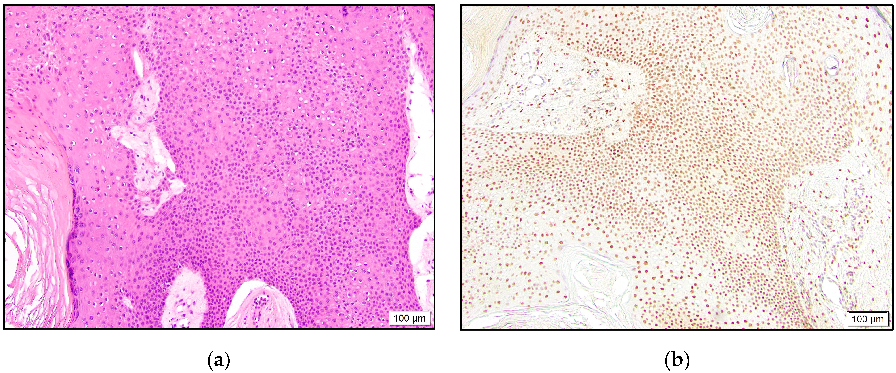

All MAC and syringoma cases were negative for TRPS1 expression (Figure 6).

Figure 6.

Infiltrative growth pattern of MAC with cords of small cuboidal cells and occasional duct formation (a). Negative TRPS1 staining in malignant cells and dermal mesenchymal cells, with positive staining (b). Well-circumscribed syringoma with tadpole-shaped ducts (c). Lack of TRPS1 expression in neoplastic cells (d).